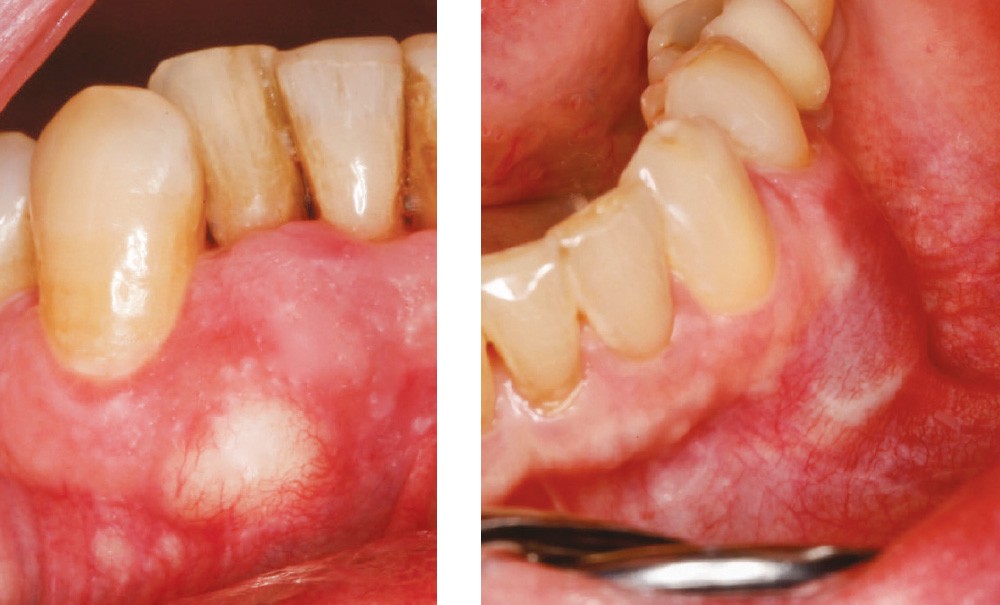

Motif de la consultation. Patient de 72 ans venu consulter sur les conseils de son hygiéniste dentaire [la prise en charge se déroule en Suisse, Ndlr] qui a remarqué la présence d’une tuméfaction gingivale vestibulaire.

Examen clinique. La tuméfaction se traduisait par une masse jaunâtre, oblongue, de 10 x 7 mm, siégeant sur la limite inférieure de la fibromuqueuse ginigivale vestibulaire entre les racines de 42 et 43. Il n’y avait aucun signe inflammatoire d’accompagnement. La palpation de la tuméfaction, non douloureuse, révélait une collection liquidienne associée à une déhiscence osseuse s’étendant surtout vers le fond du vestibule ; la corticale osseuse autour de la déhiscence n’était pas soufflée.